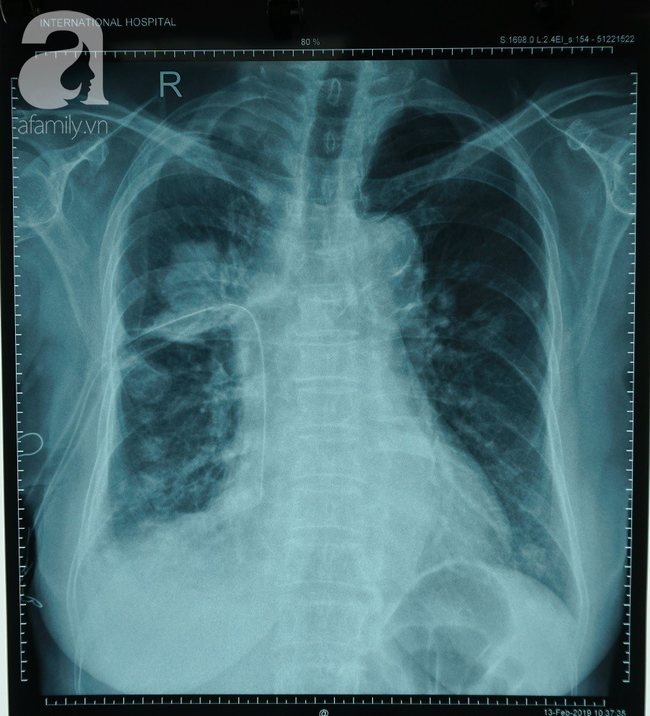

X-quang của bệnh nhân bị ung thư phổi.